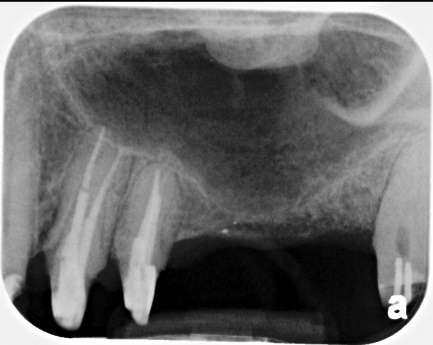

When there’s no available bone beneath the sinus floor (Fig. 1), we perform a full (external) sinus lift. We elevate the Schneiderian membrane and pack in bone graft material (Fig. 2). After 6-9 months, the new bone allows implant placement (Fig. 3). Four months later, those implants are restored with abutments and crowns (Fig. 4).

Fig. 1: No Bone Available to Receive Any Implant